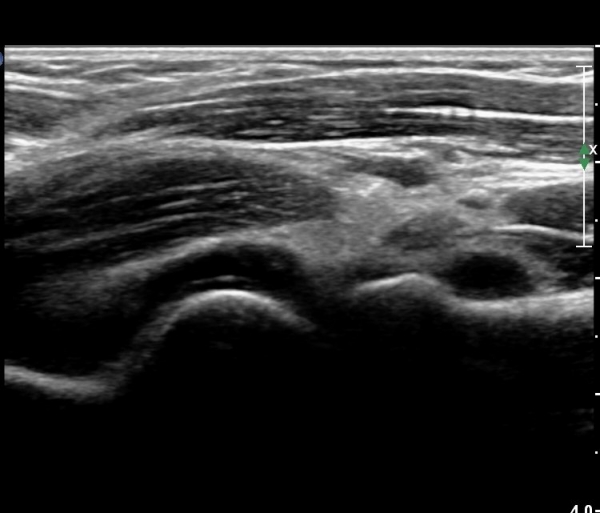

ÆÈ²ÞÄ¡ ¾ÕÂÊ ¿ÜÃø, ¼ÒµÎ(capitulum) Á¾´Ü¸é°Ë»ç¿¡¼­ ¼ÒµÎ Àü¸éºÎ¿Í ¿ä°ñµÎ Àü¸é¿¡ ¼ö¾×Àú·ù°¡ °üÂûµÊ(»çÁø 3, 4).

¼ÒµÎ Ⱦ´Ü¸é°Ë»ç¿¡¼­µµ ¼ÒµÎ Àü¸é¿¡ ¼ö¾×Àú·ù°¡ °üÂûµÊ(»çÁø 5).